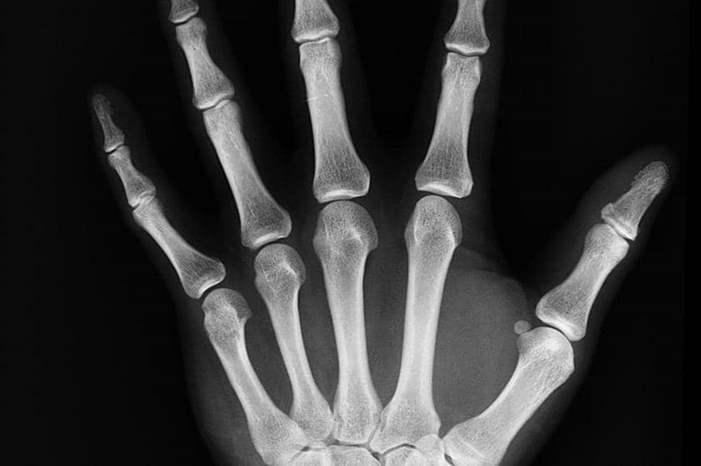

يمكن للأطباء الحصول على صورة أشعة سريعة للتأكد من أن كثافة العظام سليمة. ويساعد هذا الفحص في تحديد مخاطر الإصابة بمرض هشاشة العظام والكسور.